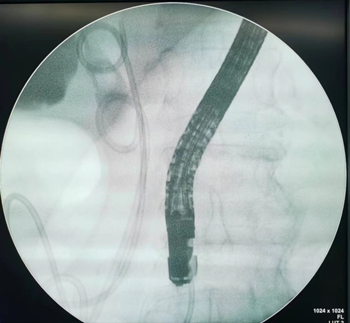

在迅速完善术前准备后,消化内科主任杨晓军主任和副主任王征球为患者实施了内镜下逆行胰胆管造影+胆道塑料支架置入+鼻胆管引流术。术中,杨晓军主任成功地将导丝插入了胆总管,完成切开、引流、造影、放置支架等一项项操作。考虑到患者血压不稳定,为了缩短手术时间,保障患者生命安全,杨晓军主任迅速放置了胆道支架及鼻胆管后退镜。手术全程仅用时20分钟,术后患者病情平稳,恢复良好。